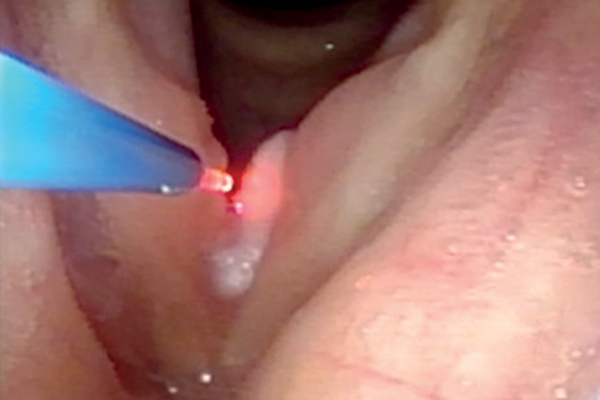

KTP laser in the office

Recurrent respiratory papilloma treatment in the office

Percutaneous fibre guided laser surgery of the endolarynx